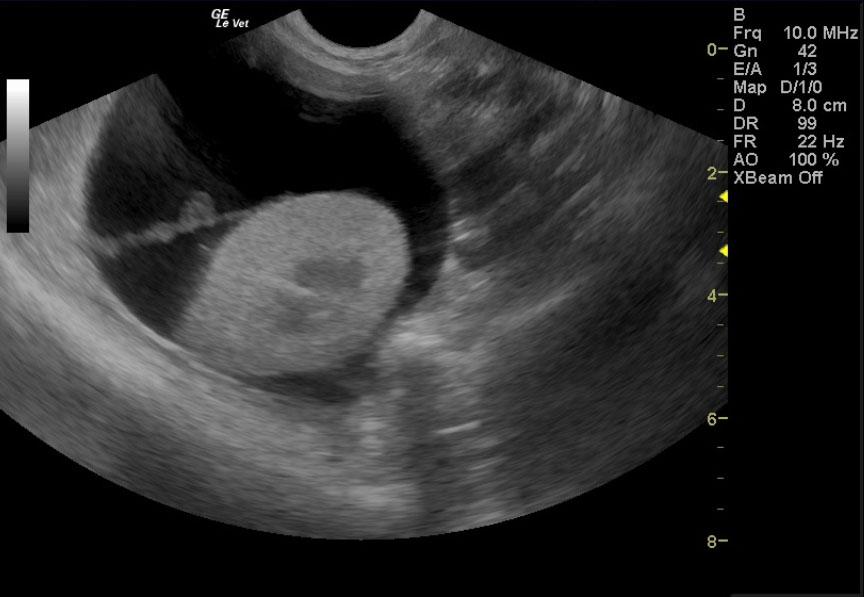

A 17-year-old neutered male DSH cat was presented to the emergency clinic with open-mouth breathing suspected to be secondary to stress/pain as the patient improved on analgesics. On a prior physical examination, an abdominal mass had been palpated.